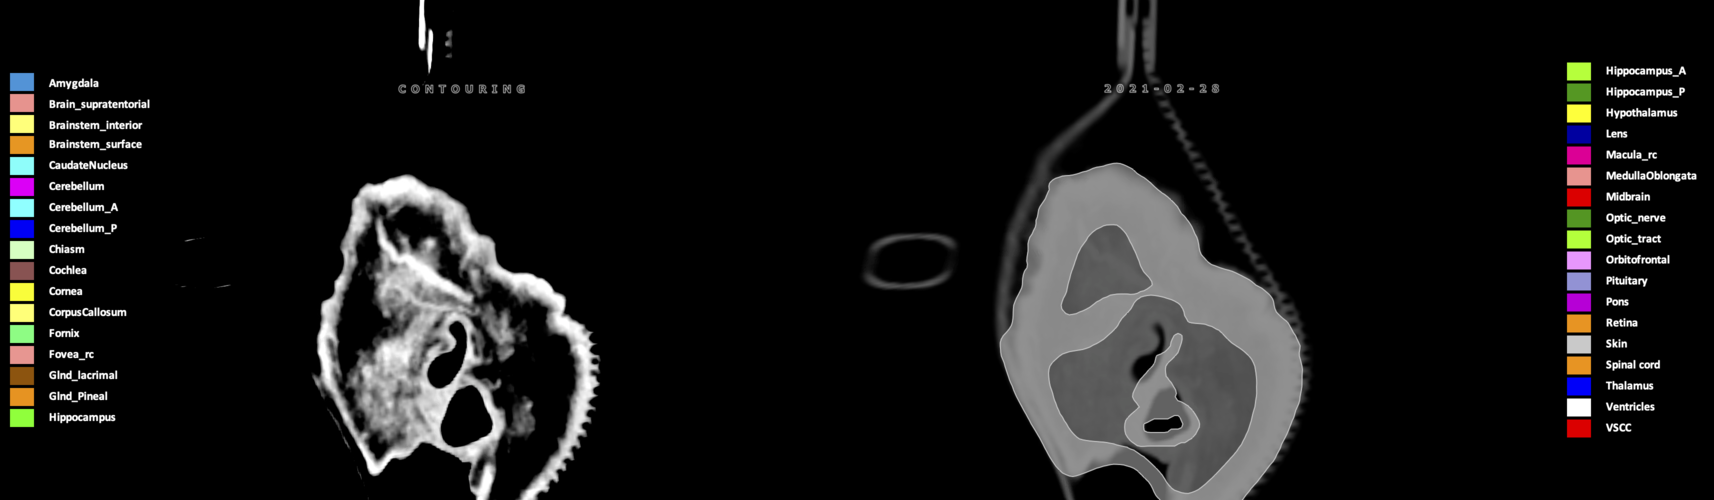

Eekers et al. have published an international neurological atlas for contouring of organs at risk in consensus with the European Particle Therapy Network (EPTN) in 2018 and an update in 2021. The purpose of this consensus atlas is to decrease inter- and intra-observer variability in delineating OARs relevant for neuro-oncology.

Included are all OARs known to be relevant for radiation-induced toxicity in neuro-oncology: brain, brainstem (midbrain, pons, medulla oblongata), chiasm, cerebellum (anterior & posterior), cochlea, cornea, hippocampus (anterior & posterior), hypothalamus, lens, lacrimal gland, optic nerve, pituitary, skin, and vestibular & semicircular canals. To further facilitate research on cognition, vision and radiological changes after irradiation of the brain, potential clinically-relevant OARs are included: amygdala, caudate nucleus, cerebellum (anterior & posterior), corpus callosum, fornix, macula, optic tract, orbitofrontal cortex, periventricular space (PVS), pineal gland, and thalamus.

We propose this atlas is used in photon and particle therapy in order to derive consistent dosimetric data. When required this atlas will be updated according to new insights.

Three-dimensional delineation of the 25 consensus OARs for neuro-oncology are shown on CT (WW/WL 120/40, 3000/600), 3T MR images, (T1Gd, T2FLAIR 1mm) and 7T MR (MP2RAGE 0.7 mm). All are presented in transversal, sagittal and coronal view.